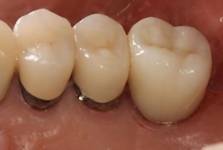

インプラント上部構造(冠)

写真右端はジルコニア冠、中央は金属焼付けポーセレン冠。インプラント上部構造はネジの緩み、ネジの破折などに備えて取り外しできるセメントで付けています。中央に光って見える小突起は、取り外しの時引っ掛けるためのものです。インプラントは咬耗に伴う挺出がないので、ここ数年は

擦り減らないジルコニアを使っています。